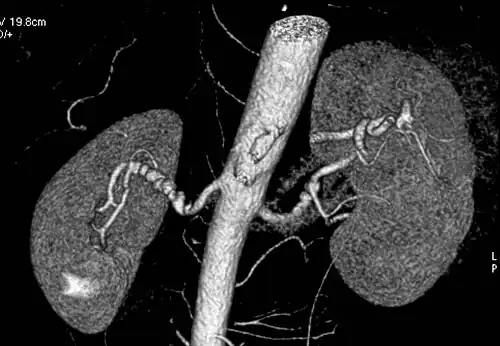

Renal arteries

Visualization of blood flow in the renal arteries (those supplying the kidneys) in patients with high blood pressure and those suspected of having kidney disorders can be performed using CTA. Stenosis (narrowing) of a renal artery is a cause of hypertension (high blood pressure) in some patients and can be corrected. A special computerized method of viewing the images makes renal CT angiography a very accurate examination.[6]

CTA is also used in the assessment of native and transplant renal arteries.[3] Recent developments have also explored the use of dual-energy CT angiography (DE-CTA) in renal imaging. This technique allows improved visualization of vascular calcifications, perfusion characteristics, and tissue composition without requiring additional contrast doses. Studies suggest that DE-CTA may enhance diagnostic confidence in differentiating between benign and malignant renal masses, as well as in characterizing complex vascular abnormalities. While CTA is great for imaging of the kidneys, it lacks the ability to perform procedures at the same time. Thus traditional catheter angiography is used in cases of acute renal hemorrhage or acute arterial obstruction.[2]